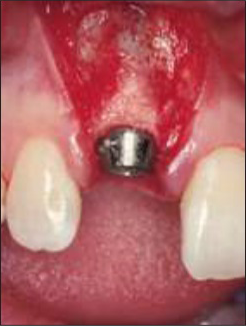

Отличная первичная стабилизация была достигнута с помощью имплантата Straumann Tapered Effect (внутрикостный диаметр 3,3 мм, длина 12 мм, ортопедическая платформа Regular Neck 4,8 мм — Рис. 9–11).

Рисунок 9 | Имплантат установлен, трансфер зафиксирован, показано правильное мезиодистальное и окклюзионно-пришеечное соотношение.

Рисунок 10 | Будущий мягкотканный профиль коронки, определяемый для постановки имплантата в идеальное короноапикальное положение.

Рисунок 11 | Окклюзионный вид имплантата с закрепленным трансфером, показывающим правильное щечно-язычное положение.